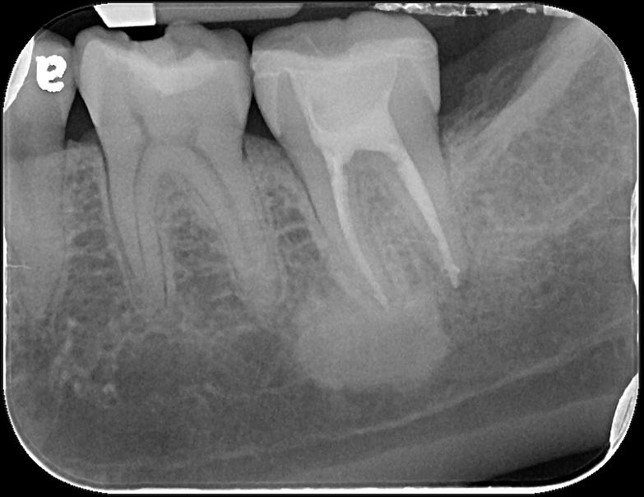

治療前,牙齒蛀牙至牙髓

牙髓受侵犯

顯微根管治療